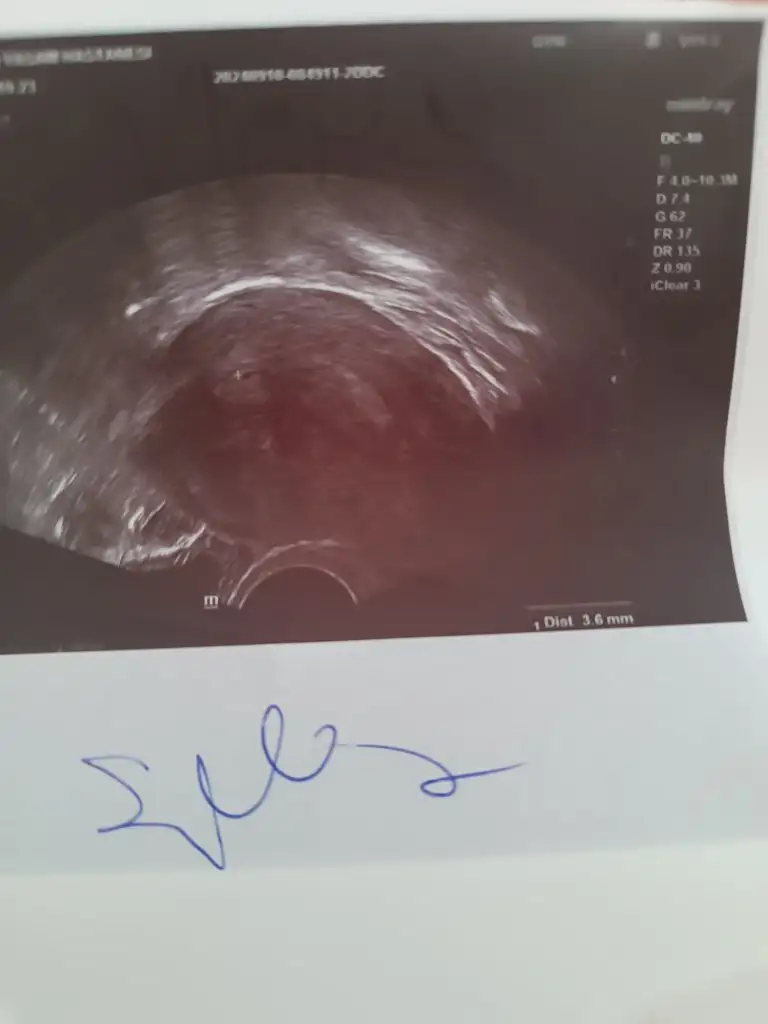

gulmra Aktif Üye Kayıtlı Üye 25 Ekim 2022 1.173 943 73 30 10 Eylül 2024 Konu Sahibi Konu Sahibi gulmra #24 Kızlar hastaneden geldim doktor kese tam göremedim dedi çok küçük bişey gördü ama kese olup olmadığını anlayamadım dedi bı bakabilir misiniz Eklentiler 1000206921.webp 12,3 KB · Görüntüleme: 43

Kızlar hastaneden geldim doktor kese tam göremedim dedi çok küçük bişey gördü ama kese olup olmadığını anlayamadım dedi bı bakabilir misiniz